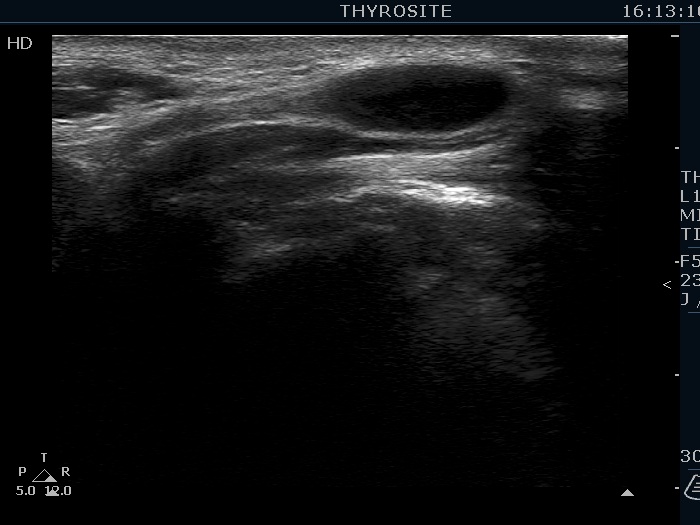

Ultrasonography. The thyroid was echonormal. There were several hypoechoic nodules in the left lobe. The middle one had back wall cystic figures. There were 3 or four discrete, deeply hypoechoic lesions above and lateral to the left lobe in the neck. One of them presented with a hilum-like figure while the others lacked hilum.

The lymph nodes had a non-typical presentation. They lacked a regular hilum.